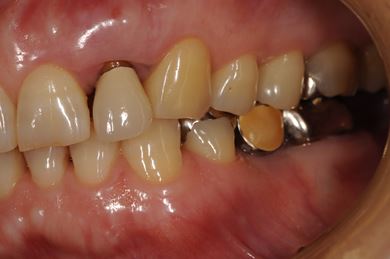

インプラントの症例写真 IMPLANT

骨再生スピードインプラント治療+セラミック治療

| 性別/年齢 | 女性 / 58歳 | ||||||||||||||||||||||||||||||||

| 主訴 | 左上前歯となりがゆらついている。他院でインプラントが必要と言われ、相談に来ました。 | ||||||||||||||||||||||||||||||||

| 治療方針 | 骨再生法によりインプラント治療を可能にする。抜歯と同時にインプラント埋入を行い、治療期間を短縮する。 | ||||||||||||||||||||||||||||||||

| 治療内容 | インプラント3本(抜歯即日スピードインプラント、GBR)、メタルボンドセラミッククラウン1本、ハイブリッドセラミッククラウン4本(ハイブリッドセラミック用土台1本) | ||||||||||||||||||||||||||||||||